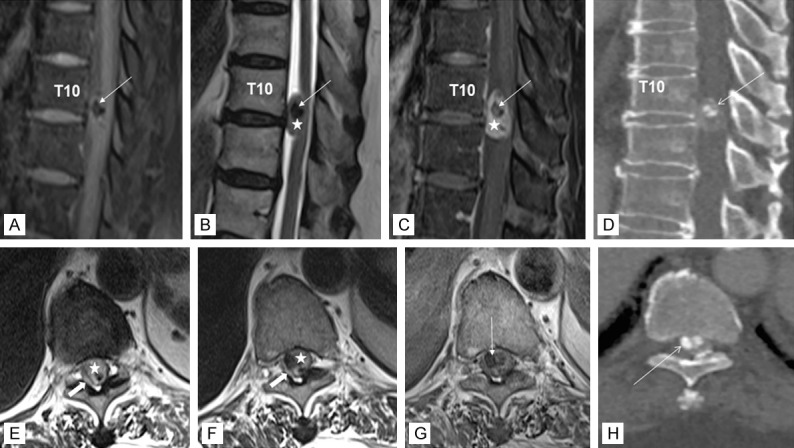

Magnetic resonance imaging (MRI) of the spine revealed a 16 mm well-defined intradural extramedullary lesion at T10/T11 level, compressing the adjacent spinal cord. Remarkably, noticeable hypointense signal was seen centrally on T1- and T2-weighted sequences, representing intratumoral calcification (Figure 1). In addition, there were multilevel extensive degenerative disc changes of the spine with protrusion of osteophyte-discal complex from C3 to C7, most severe at the C5/C6 level with associated significant spinal canal stenosis and cord compression (not shown), corresponding to the neurological impairment elicited. Computed topography (CT) examination of the spine demonstrated a highly attenuating intratumoral calcification within the spinal canal, in agreement with the MRI finding (Figure 1). She underwent a left T10 hemilaminectomy and excision of the intradural extramedullary mass. The tumor was removed piecemeal successfully with minimal adherence to surrounding structures. No residual disease was detected by postoperative MRI.

Figure 1.

MR imaging of the thoracic spine in T1-weighted image with fat saturation (A), T2-weighted image (B), T1-weighted fat saturation post contrast image (C), and CT bone setting reconstruction image in sagittal plane (D) and T2-weighted image (E, F), T1-weighted post contrast image (G), and CT reconstruction image in bone setting in axial plane (H). The intradural extramedullary lesion (star) exhibits isointense signal on T1, is hyperintense on T2, and enhances homogeneously with contrast. There are hypointense foci within (arrow) that are markedly hypointense on T1 and T2 consistent with intratumoral calcification as shown in the CT images. The spinal cord is displaced and compressed right posterolaterally by the mass and returns high signal intensity on T2 indicating cord edema (block arrow).